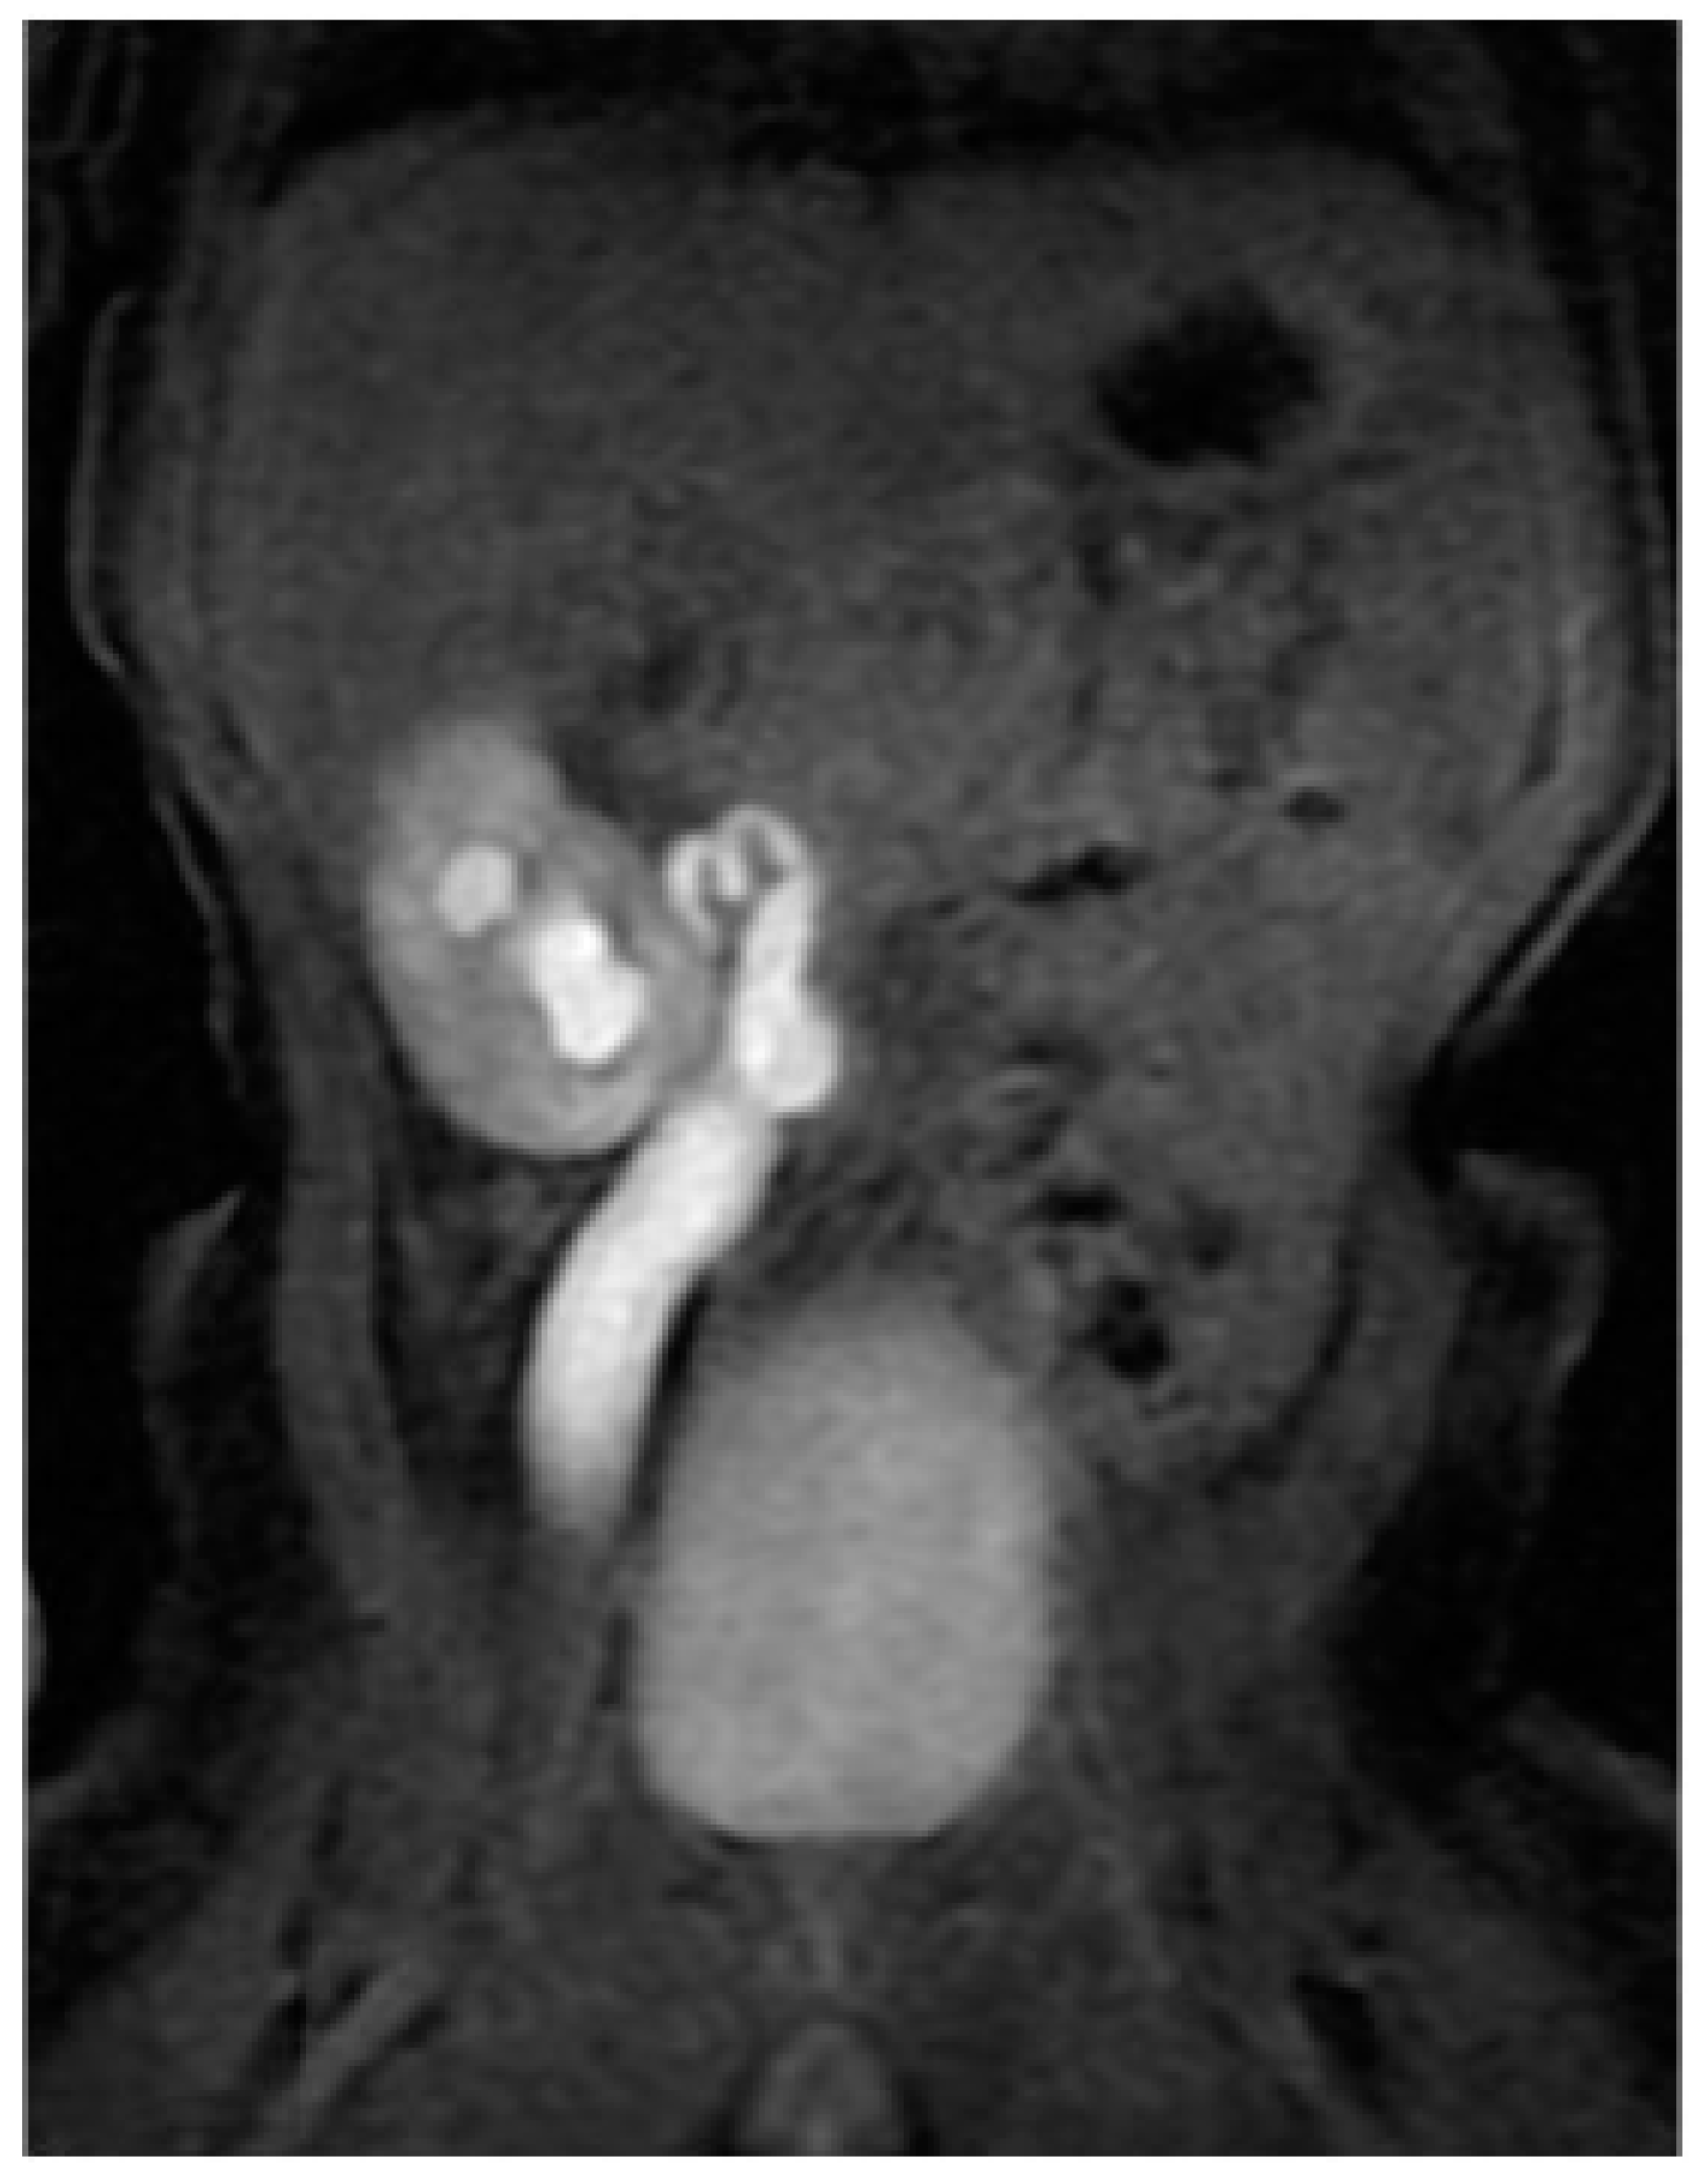

In order to treat the acute spontaneous rupture of the renal pelvis and ascites, an abdominal drain was placed through an umbilical incision and a retrograde pyelogram was performed, showing a right primary obstructive megaureter (POM) associated with a corkscrew pyeloureteral junction (PUJ) (Figure 2).

Figure 2.

Intraoperative retrograde pyelogram showing a right primary obstructive megaureter (cross) associated with a corkscrew pyeloureteral junction obstruction (arrow).